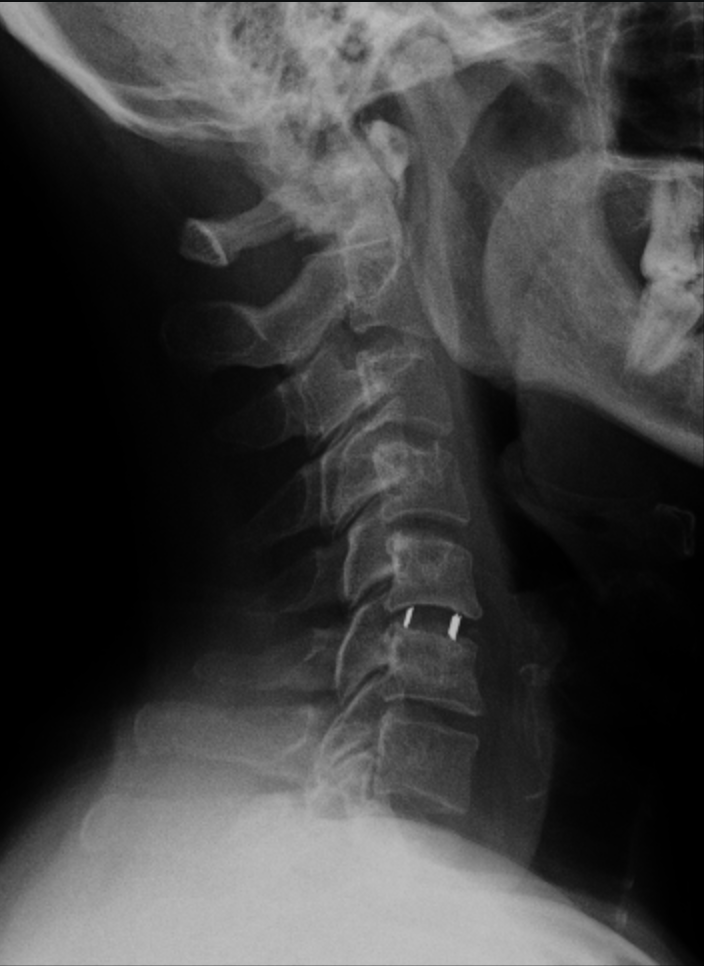

En C5-C6 cambios degenerativos con complejo disco osteofitario que condiciona estenosis moderada del canal raquídeo cervical, apreciando signos de mielopatía compresiva. Estenosis foraminal bilateral moderada en C5-C6 e izquierda leve en C6-C7 |

Se aprecia la prótesis de disco colocada entre C5 y C6 | ||||